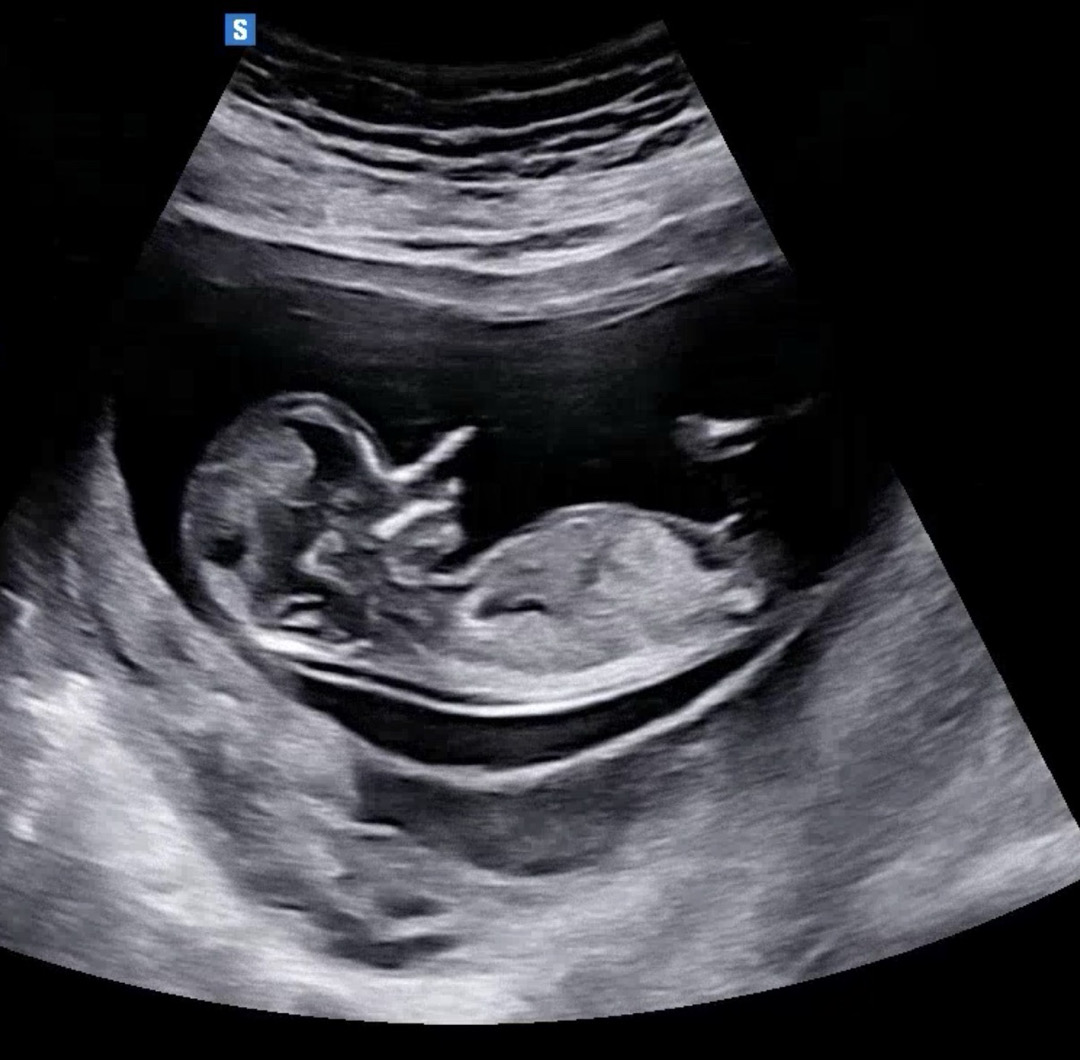

12주 3일 성별이요

알수있을까요?

우리 아기 성별이 궁금하다면?

초음파 사진을 올리면 AI가 무료로 예측해줘요